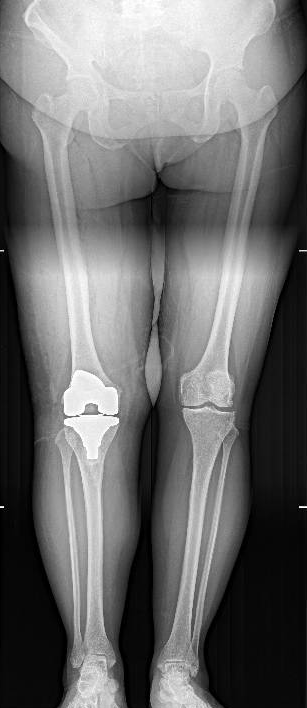

术后观察:术后通过X光片观察手术效果,假体植入状态良好,力线恢复正常。